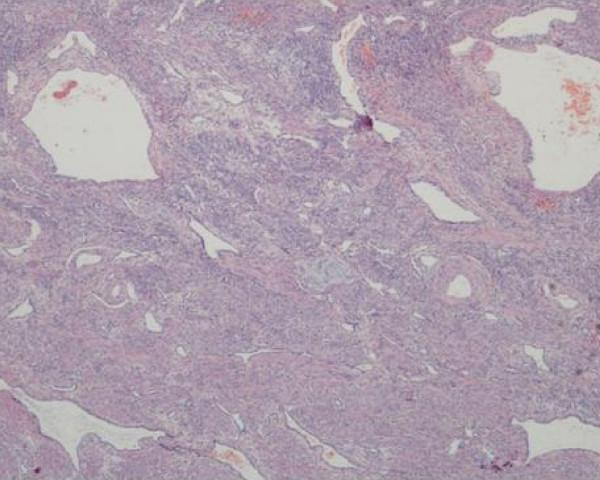

We report a case of cavernous hemangioma of the uterus in a 27-year-old Malay, para 1 woman who presented at our hospital with torrential vaginal bleeding having been transferred by land ambulance from a district hospital 30 minutes away. 11 weeks previously she had an urgent cesarean section at our hospital. She had to undergo a hysterectomy to control her bleeding after other measures were unsuccessful. A histopathological report confirmed a diffuse ramifying hemangioma of the cervix and uterus with left hematosalpinx.

我们报告一例27岁经产妇、马来族女性的子宫海绵状血管瘤病例,该患者由30分钟车程外的一家地区医院通过陆路救护车转送至我院,当时出现大量阴道出血。11周前她在我院接受了急诊剖宫产。在其他措施均未成功后,她不得不接受子宫切除术以控制出血。组织病理学报告证实为宫颈和子宫弥漫性分支状血管瘤伴左侧输卵管积血。